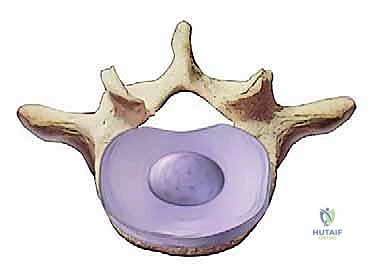

1. الجسم الفقري (Vertebral Body): الكتلة العظمية الأسطوانية الكبيرة في الجزء الأمامي من الفقرة، وهي التي تتحمل الضغط.

2. القرص بين الفقرات (Intervertebral Disc): يعمل كوسادة لامتصاص الصدمات بين الأجسام الفقرية. يتكون من:

* الحلقة الليفية (Annulus Fibrosus): الغلاف الخارجي القوي والمرن.

* النواة اللبية (Nucleus Pulposus): المركز الهلامي الناعم الذي يوفر خاصية امتصاص الصدمات.

فهم أمراض القرص التنكسية (Degenerative Disc Disease - DDD)

أمراض القرص التنكسية ليست "مرضاً" بالمعنى التقليدي، بل هي مصطلح يصف التغيرات الطبيعية التي تحدث في الأقراص الفقرية مع تقدم العمر، والتي تتطور لدى بعض الأشخاص لتصبح مصدراً لألم شديد ومستمر.

كيف يحدث تنكس القرص؟

في مرحلة الشباب، تكون الأقراص الفقرية ممتلئة بالماء، مما يجعلها مرنة وقادرة على أداء وظيفتها كمرتبة مائية تمتص الصدمات. مع مرور الوقت، أو بسبب الإجهاد المتكرر، تبدأ هذه الأقراص في فقدان محتواها المائي (الجفاف).

يؤدي هذا الجفاف إلى:

* فقدان ارتفاع القرص: مما يقلل المسافة بين الفقرات، ويؤدي إلى تضيق الثقوب العصبية (المخارج التي تمر منها الأعصاب).

* تمزقات في الحلقة الليفية: قد تتمزق الألياف الخارجية للقرص، مما يسبب ألماً موضعياً شديداً.

* بروز أو انفتاق القرص (الانزلاق الغضروفي): قد تندفع النواة اللبية عبر التمزقات وتضغط على جذور الأعصاب.

* تكون النتوءات العظمية (Osteophytes): كرد فعل على عدم الاستقرار، يحاول الجسم تثبيت العمود الفقري عن طريق نمو عظام إضافية، والتي للأسف قد تضيق القناة الشوكية وتضغط على الأعصاب بشكل أكبر.